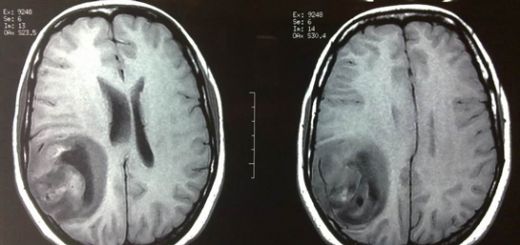

Tanı Yöntemleri İyi huylu beyin tümörlerinin tanısı, genellikle aşağıdaki yöntemler kullanılarak konulmaktadır: